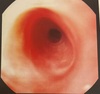

Esôfago típico de

Esofagite herpetica: múltiplas úlceras superficiais